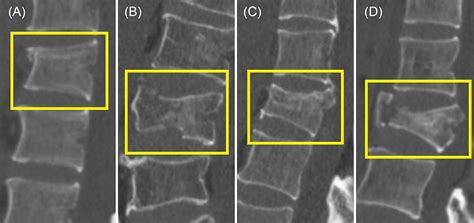

Based on the Pattern of the Break

The physical appearance of the break on an X-ray determines its classification:

• Transverse Fracture: A break that occurs at a right angle to the long axis of the bone.

• Oblique Fracture: A break that occurs at an angle across the bone.

• Spiral Fracture: A break that spirals around the bone; often caused by a twisting force.

• Comminuted Fracture: A break where the bone shatters into three or more pieces.

• Greenstick Fracture: Common in children, where the bone bends and cracks but does not break completely through.